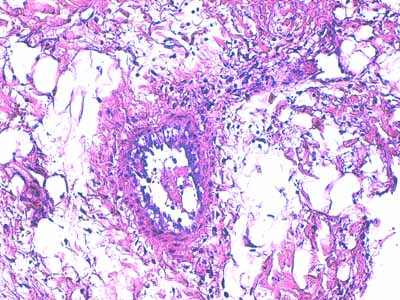

Photo 9 (Hémalun-Eosine X200) : une artériole hypodermique de moyen calibre

montre une vacuolisation de ses cellules endothéliales et un épaississement

de sa media et de son adventive. Sa lumière abrite un fragment de

thrombus fibrineux. L’hypoderme environnant est œdémateux.

Légendes de la Photo 9 :

- Flèches jaunes : vésiculation de l’espace sous-endothélilae et des cellules endothéliales

- Flèches turquoises : œdème et infiltrat neutrophilique dilacérant les adipocytes des lobules adipeux de l’hypoderme

- Pointe de flèche turquoise : adipocyte

- Ovale rouge pointillé : artériole de moyen calibre

- Ronds verts : endothélium de l’artériole

- Ronds noirs : media de l’artériole

- Ronds bleus : adventice de l’artériole

- Double flèche bleue : hypoderme

- Étoile rouge : thrombus fibrineux ostruant la lumière de l’artériole